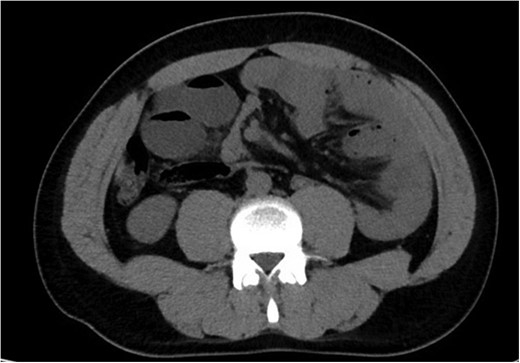

The patient presented to a local hospital at approximately mid-day with worsening severe central abdominal pain associated with vomiting and obstipation. The symptoms had been rapidly progressing over a period of 12 h. He finally presented with pain preventing him from lying flat. Patient had no history of abdominal surgery, trauma or large food bolus. There was no other relevant past personal or family history. On examination, he appeared diaphoretic and in distress, but maintained normal vital signs, except for bradycardia. His examination revealed signs of florid peritonism, with rigid distended abdomen. Initial blood films were only remarkable for hypophosphatemia (0.33 mmol/L) with a normal lactate (1.1 mmol/L) and pH (7.30 with base excess of −3 mmol/L). His white cell count was 11.8 × 109, and had a C-reactive protein of 14. An abdominal computed tomography (CT) scan was performed and revealed features highly suggestive of mid-gut volvulus with associated obstruction and likely vascular compromise (Figs 1 and 2).

Axial CT abdomen and pelvis revealing internal hernia with evidence of small bowel obstruction.